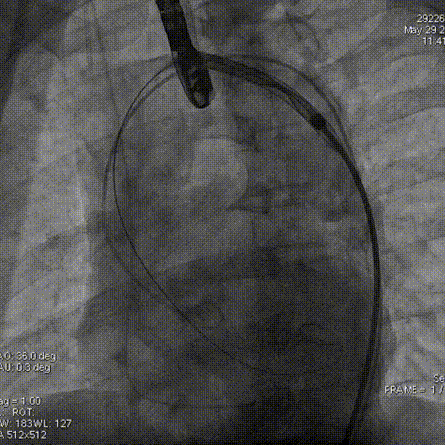

输送器过弓

瓣膜定位

1.考虑到患者瓣叶增厚,重度钙化,需要更强的径向力锚定,预装AV29瓣膜。

2.根据术前CT评估,跨瓣角度为RAO 16°CAU 35°(近左右重合位)左右,球囊预扩角度为LAO 16°CRA 3°(左冠切线位)左右,释放角度为RAO 16°CAU 35°(近左右重合位)左右。使用22mm球囊预扩,充分利用沛嘉TaurusElite产品可回收的功能,瓣环上0mm高度释放.